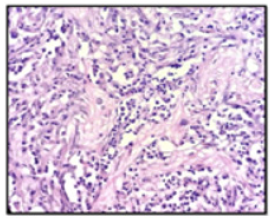

Figure 1: Spindled myofibroblasts and fibroblasts without atypia, surrounded by the inflammatory cells (HESx40).